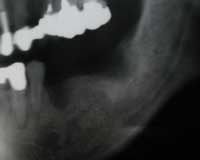

| 術前 | ソケットリフト手術 | 術後2年歯根周囲骨造成良好 |